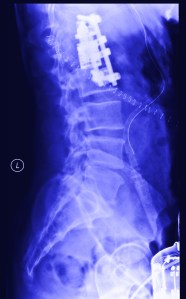

four years ago this month I fell (pretty seriously) but- I bounced.

time at this point stretched itself outup- into minute by minute segments and continued for a few months like this- there was no ‘bounce’ apparent at this point. It’s probably more like you have to crawl out of whatever crater you made on impact and you are just trying to get back to the surface-I started to keep a journal when I got out of the hospital- many many days it just says what time I got up and maybe how I felt (in like 2 or 3 words) but eventually I had entries about dressing myself and then an entry about how I would eventually stop making entries- and not to worry because I was getting better.